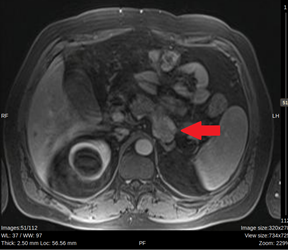

Figure 1: Abdominal MRI. Red arrow: Exophytic tumor in the posterior sector of the pancreatic body.

MRI showed a pancreas of normal size and morphology. In the posterior body of the pancreas, a 30 mm solid exophytic nodule was observed, with diffusion restriction and intense arterial phase enhancement persisting in late phases. Wirsung duct was normal. (Figure 1)